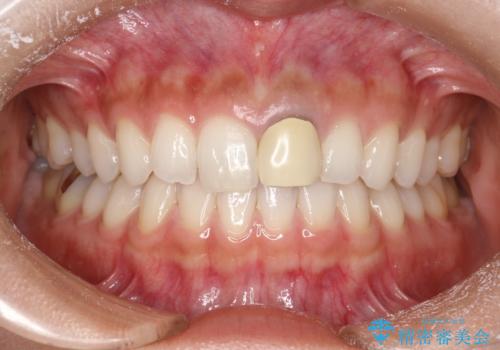

前歯のかぶせ物の色があっていない オールセラミック治療

- 以前装着された前歯のかぶせ物の色を変えたいとのことで来院されました。

土台からの再治療を行い、オールセラミッククラウンを装着する治療計画としました。